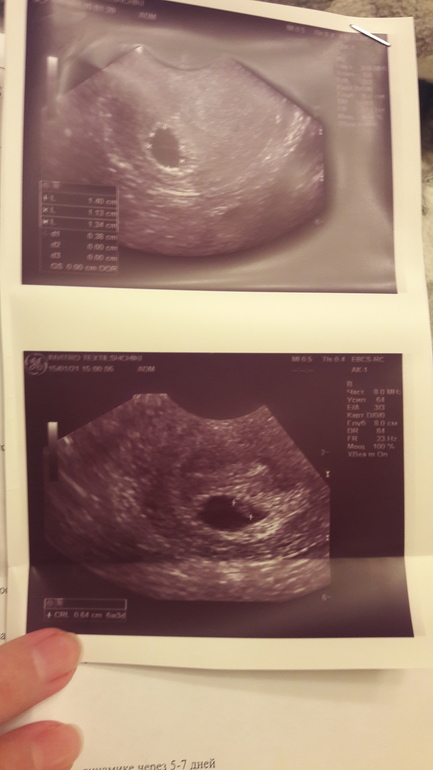

ДД. Знаю что тема заезжена, Но что поделать. Я на 90% уверена что замерла беременность написала своей Г, она типа хватит выдумывать жди до понедельника... впереди выходные как то стремно. Пошла к другой, она тоже какое сердцебиение еще рано🤤 Совсем блин не рано, говорю на прошлом узи 11.01 была пульсация, а на ее аппарате (который вроде как лучше) не сердцебиения ни пульсации((( Все равно доказывает что еще рано может вы газы! в прошлое узи видели🤦♀️ Бред вообщем... Говорит как замерла размеры увеличились: 11.01 свд 10 ктр 4; 15.01 свд 13 ктр 6. почему она пишет живой эмбрион если ничего не увидела? Не знаю вобщем что и думать....Илона Исаева